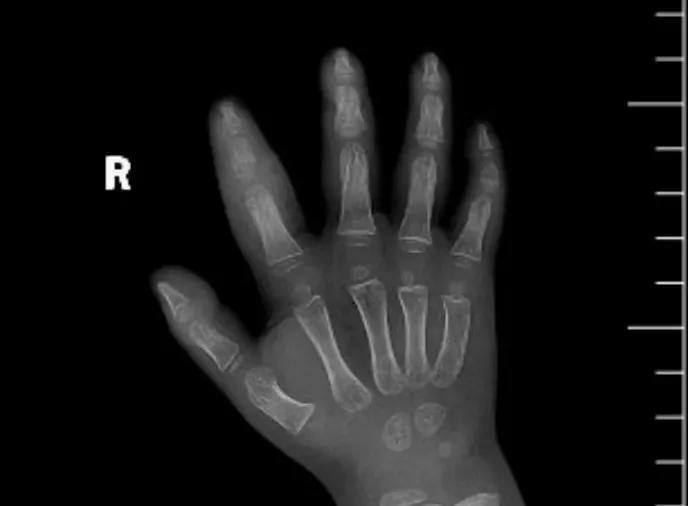

近日,市二院顯微外科接診一名3歲半的小患者,被玉米葉割傷右食指,因家長(zhǎng)疏忽大意,導(dǎo)致一個(gè)小小的傷口竟然發(fā)展成了骨髓炎。來(lái)院時(shí)患兒右食指腫脹明顯,既不能伸也不能彎,皮膚發(fā)燙,疼得哇哇大哭。

第三天開(kāi)始,月月哭鬧不止,一直說(shuō)手疼,怎么哄也不行,于是在當(dāng)?shù)蒯t(yī)院治療了10來(lái)天,然而月月的手指依然腫得像個(gè)胡蘿卜,疼痛感依然存在。此時(shí),月月的媽媽才覺(jué)得事情不大對(duì)勁,于是經(jīng)過(guò)打聽(tīng),慕名來(lái)到市二院顯微外科。入院后,經(jīng)檢查發(fā)現(xiàn),月月的右食指骨質(zhì)有侵蝕,骨骺有缺損,甚至?xí)绊懸院笫种傅陌l(fā)育。聽(tīng)到這個(gè)消息,月月媽媽感覺(jué)心都揪住了。

隨后,經(jīng)顯微外科團(tuán)隊(duì)充分的討論,制定了科學(xué)細(xì)致的治療方案,為月月做了感染灶清除及手指的開(kāi)放引流,并留取了標(biāo)本做細(xì)菌培養(yǎng),為進(jìn)一步的合理用藥提供依據(jù)。經(jīng)過(guò)兩周的治療,月月的手指終于順利消腫愈合,并且手指功能活動(dòng)良好。說(shuō)起這一個(gè)多月的煎熬,月月媽媽不禁落淚,但總算是治愈了,笑容又重新回到她們一家的臉上。